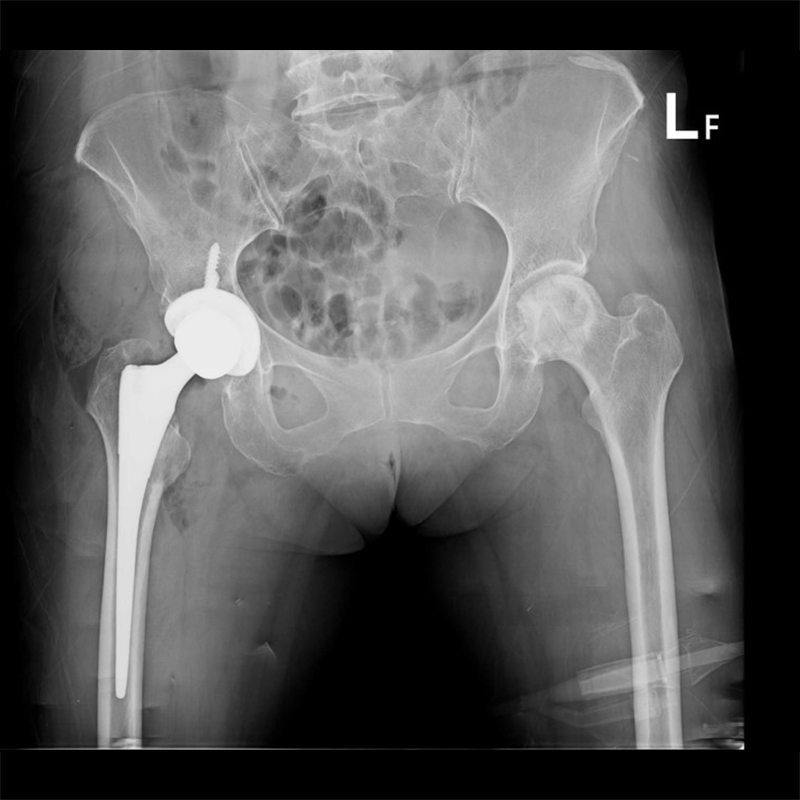

傳統髖關節置換 首頁 案例分享 髖關節手術 傳統髖關節置換 54歲蔡先生退化性關節炎 術前 術後 張女士 51歲 退化性關節炎(DDH先天發育不全 CROWE TYPE 2) 術前 術後 38歲林先生 退化性關節炎 術前 術後 72歲謝女士 退化性關節炎 術前 術後 71歲 謬女士 骨股頭壞死 術前 術後 50歲 郭先生骨股頭壞死 術前 術後 80歲 盧先生骨股頭壞死 術前 術後 林先生 37歲 術前 術後 邱女士 51歲 術前 術後 張女士 50歲 術前 術後